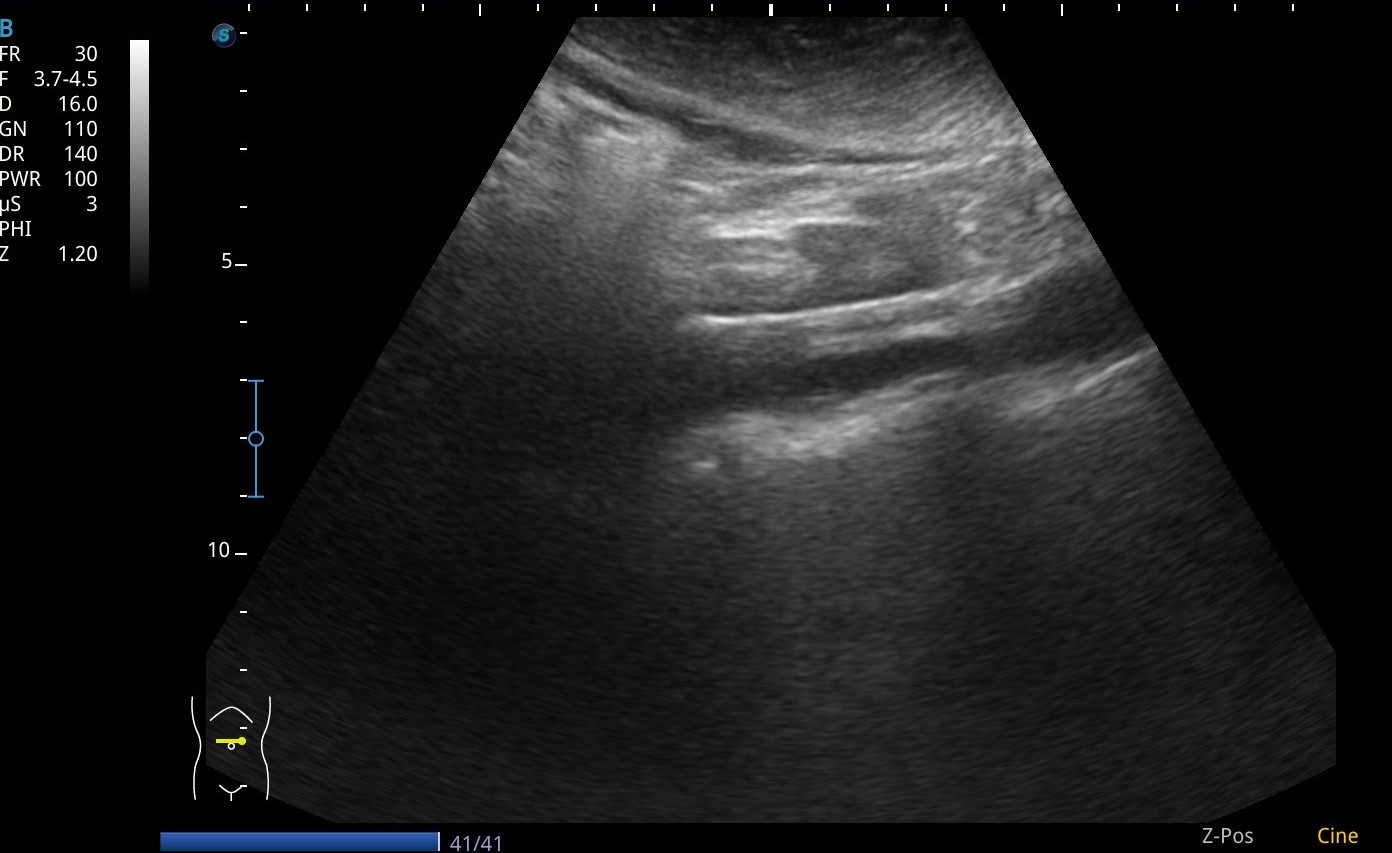

Se realiza ecografia a pie de cama que muestra como en el flanco derecho presenta silueta renal con un polo superior visible, sin poder definir el polo inferior, y la misma imagen en la silueta renal izquierda.

Asi mismo vemos a nivel de epigastrio bajo (zona umbilical), tejido sugestivo de parénquima renal que cruza por delante de grandes vasos, imagen compatible con un riñon en herradura.

En pelvis renal izquierda se aprecia una imagen hiperecogénica, sugestiva de microlitiasis.